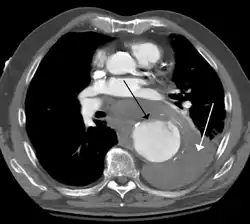

- Contrast enhanced CT of a ruptured large (7 cm) thoracic aneurysm, with black arrow indicating the aorta, and white arrow blood in the thorax